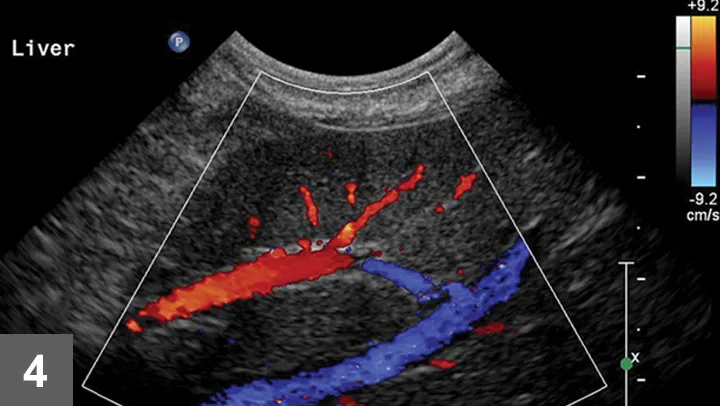

Once the image area is optimized, turn on color flow Doppler to ensure there are no major vessels in the area of interest (Figure 4). The hepatic and portal veins—but not the distribution of the hepatic artery—can be visualized on a standard gray-scale 2-dimensional ultrasound image. Angle to the right and left to ensure that there are no major vessels within the target area. Turn off imaging compounding to ensure accurate needle-tract and needle-tip placement at depth in the liver.

Color Doppler of a potential biopsy area in the liver. On account of the presence of large portal veins (colored in red—flow toward the transducer) and hepatic veins (colored in blue—flow away from the transducer), this area was not chosen for biopsy.